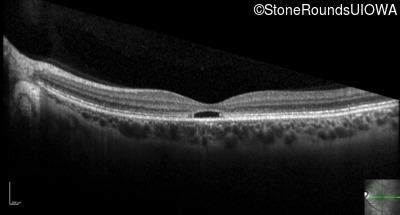

Optical Coherence Tomography - Right - 20/20 -1

Exemplar / OCT Stack